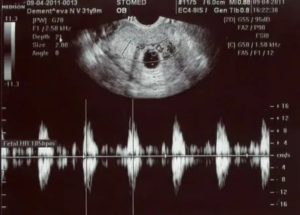

Вид эмбриона в 7 недель напоминает форму фасолины, а размеры плода колеблятся в пределах 7-11 мм. На 7 неделе с помощью ультразвуковой диагностики можно услышать сердцебиение плода, определить количество ударов.

Благодаря ультразвуковому исследованию можно определить биение сердца плода. Трансвагинальное УЗИ может обнаружить сокращение сердца эмбриона раньше, чем трансабдоминальное. При помощи специального датчика, введенного во влагалище женщины, сердцебиение определяется на 5-6 неделе, а при обследовании с датчиком на животе – на 6-7 неделе.

Сколько ударов/минуту считается нормой для развивающегося плода? – это тоже весьма важный вопрос. Частота сокращений сердца изменяется на разных этапах беременности:

- 6-8-я недели – 110-130 ударов/минуту;

- 9-10-я недели – 170-190 ударов/минуту;

- 11-40-я – 140-160 ударов/минуту.